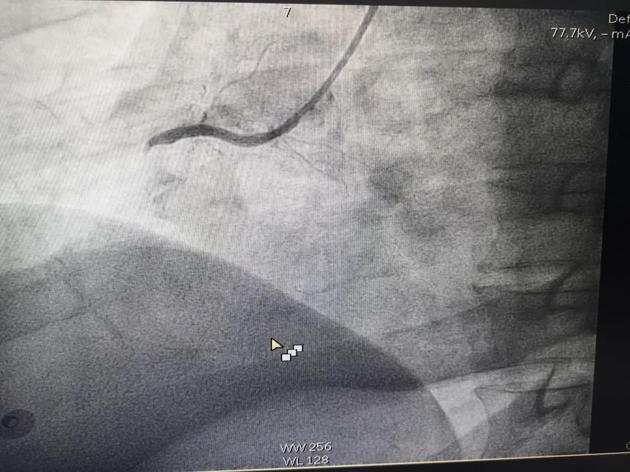

M老师在昏迷中,在各种仪器设备的强力生命支持条件下,由心血管介入团队对其完成了急诊冠脉造影检查——心脏右侧冠状动脉完全堵塞,伴有大量血栓形成!这是急性心肌梗死,需要马上手术开通血管。

堵塞的血管